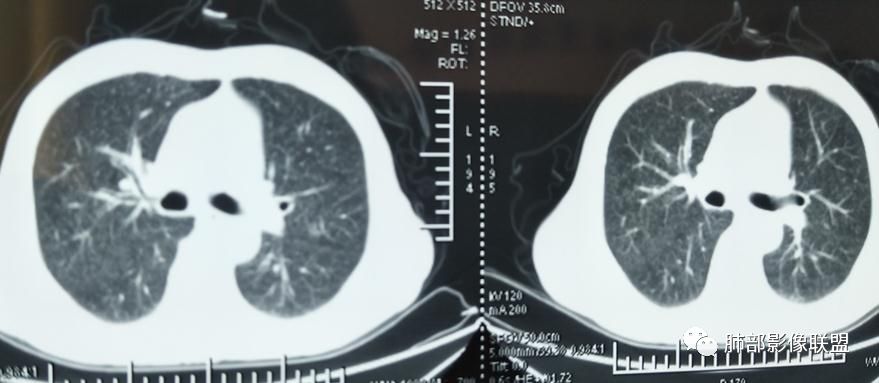

2019-10-20复查CT如下:

左上纵隔旁病灶存在

大小、分布均匀,边缘清楚

细小结节,弥漫,撒米粒样——血道来源

血道来源的病灶,均匀、细微,而且部分有分支状,都符合粟粒型肺结核

10月20日的CT其实是抗痨治疗近1月复查的CT。患者来我院后抗痨治疗体温下降,症状明显好转。

急性血行播散型肺结核  两肺广泛分布粟粒大小的结节状密度增高影,具有大小均匀、分布均匀、密度均匀的典型“三均匀”特征,注意急性血播病灶非常小,一般粟粒影直径1~2mm。